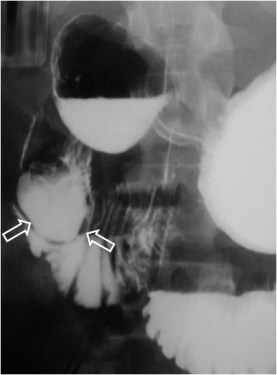

Signo de esclerodermia en el tránsito intestinal. Describe un acercamiento de las válvulas conniventes, que conservan el grosor normal, debido a dilatación de la luz intestinal (flechas blancas). Se afecta con más frecuencia el yeyuno y el íleon proximal. Este hallazgo se debe a la afectación de las capas musculares de las asas intestinales en la esclerodermia.

Semiológicamente este signo es similar al anterior, el Signo de las pilas de monedas, aunque el nombre de Signo del intestino enjuto es exclusivo de la esclerodermia.

Resulta difícil la traducción del nombre original en inglés de este signo (hide-bound bowel). En sentido figurado hide-bound significa rígido, estricto, términos que no se ajustan al aspecto de las asas en la esclerodermia. El término está tomado de la descripción de la apariencia de la piel en esta enfermedad, que se encuentra engrosada, endurecida y adherida a planos profundos, y se compara a la piel gruesa de animales domésticos como la vaca o el caballo, pegada al hueso.

El arículo de referencia es: Perry J. Pickhardt. The «hide-bound» bowel sign. Radiology 1999; 213:837-838. En: http://pubs.rsna.org/doi/full/10.1148/radiology.213.3.r99dc21837.